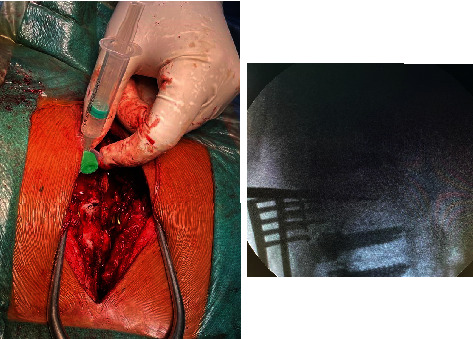

Aggressive thoracic hemangiomas are rare, benign tumors that extend into the spinal canal and cause neurological symptoms. Delayed diagnosis and treatment, due to a paucity of literature on optimal treatment strategies, can increase morbidity. This case report describes a 19-year-old male patient with aggressive thoracic hemangioma who presented with upper back pain and progressive weakness of the lower extremities. The patient underwent preoperative embolization and sclerotherapy, followed by decompression, posterior instrumentation, and stabilization. The final diagnosis was confirmed by biopsy, and there was a significant improvement in neurology after the surgical intervention. The diagnosis of rare lesions, such as aggressive hemangiomas, requires a high level of clinical suspicion and the assistance of imaging modalities in patients with features of compressive myelopathy. A combination of endovascular and surgical approaches can lead to optimal outcomes.